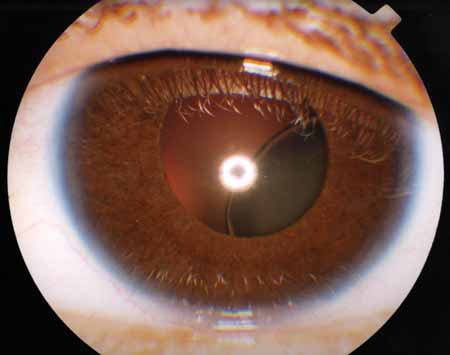

Sindrom marfana tema nauchnoj stati po klinicheskoj medicine chitajte besplatno tekst nauchno issledovatelskoj raboty v elektronnoj biblioteke kiberleninka (Тип файлу jpg)

Sindrom Marfana Tema Nauchnoj Stati Po Klinicheskoj Medicine Chitajte Besplatno Tekst Nauchno Issledovatelskoj Raboty V Elektronnoj Biblioteke Kiberleninka